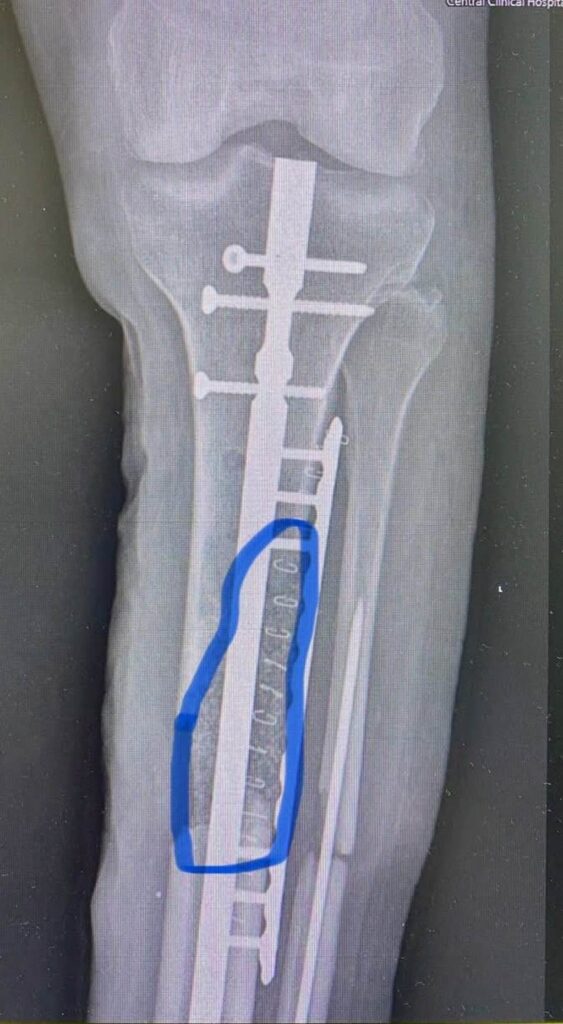

Тут вы видите рентгенограммы двух пациентов. В одном случае ранение голени у коленного сустава. В другом случае у сустава голеностопного с переломом костей. Поэтому там пластина еще стоит.

Обоим раненым (а каждый из них лечится по полгода уже) проведены по несколько операций дебридмента («чистка» кости и мягких тканей). К сожалению, это не остановило инфекцию.

В общем, все чаще и чаще приходится травматологам в Украине применять Bonalive. Это заменитель кости с антибактериальным действием. Только вот действует этот заменитель (финского производства) не за счет антибиотиков. Их в нем нет. А за счет того, что резко меняет Ph среды в кислую сторону. Бактерии погибают, привыкания к этому заменителю нет и быть не может (пока и если не появится какой-то новый, доселе неизвестный микроб), рост же собственной кости резко стимулируется.

Эти двое пациентов, чьи рентгенограммы вы видите, были прооперированы Председателем нашей Ассоциации AO Trauma Ukraine Олександром Рихтером в одном из военных госпиталей на западе Украины. Все зажило отлично.

Для первого раненого хватило 10 кубических сантиметров Bonalive, на второго – там, где пластина, ушло 20 «кубиков». Итого, в дополнение ко всему прочему – это 1500 евро.